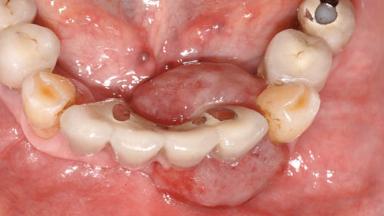

Peripheral Giant-cell Granuloma Associated with Peri-implant Tissues

# of Implants 5

Type of Implants One-Piece